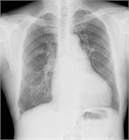

病態

1. 慢性血栓塞栓性肺高血圧症(CTEPH)[ESCガイドラインでは肺高血圧症を伴う慢性血栓塞栓性肺疾患(CTEPD with PH)という表現が用いられるようになった] は、器質化した血栓により肺動脈が慢性的に閉塞を起こし、肺高血圧症を合併するもので、労作時の息切れが特徴である。